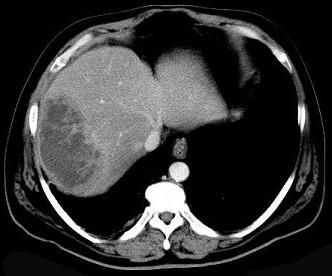

问题 细菌性肝脓肿的最常见致病菌是 ( )

选项 A、粪链球菌、金黄色葡萄球菌和厌氧菌 B、溶血性链球菌、金黄色葡萄球菌和厌氧菌 C、大肠杆菌、粪链球菌和厌氧菌 D、大肠杆菌、金黄色葡萄球菌和厌氧菌 E、大肠杆菌、绿脓杆菌和厌氧菌

答案 D